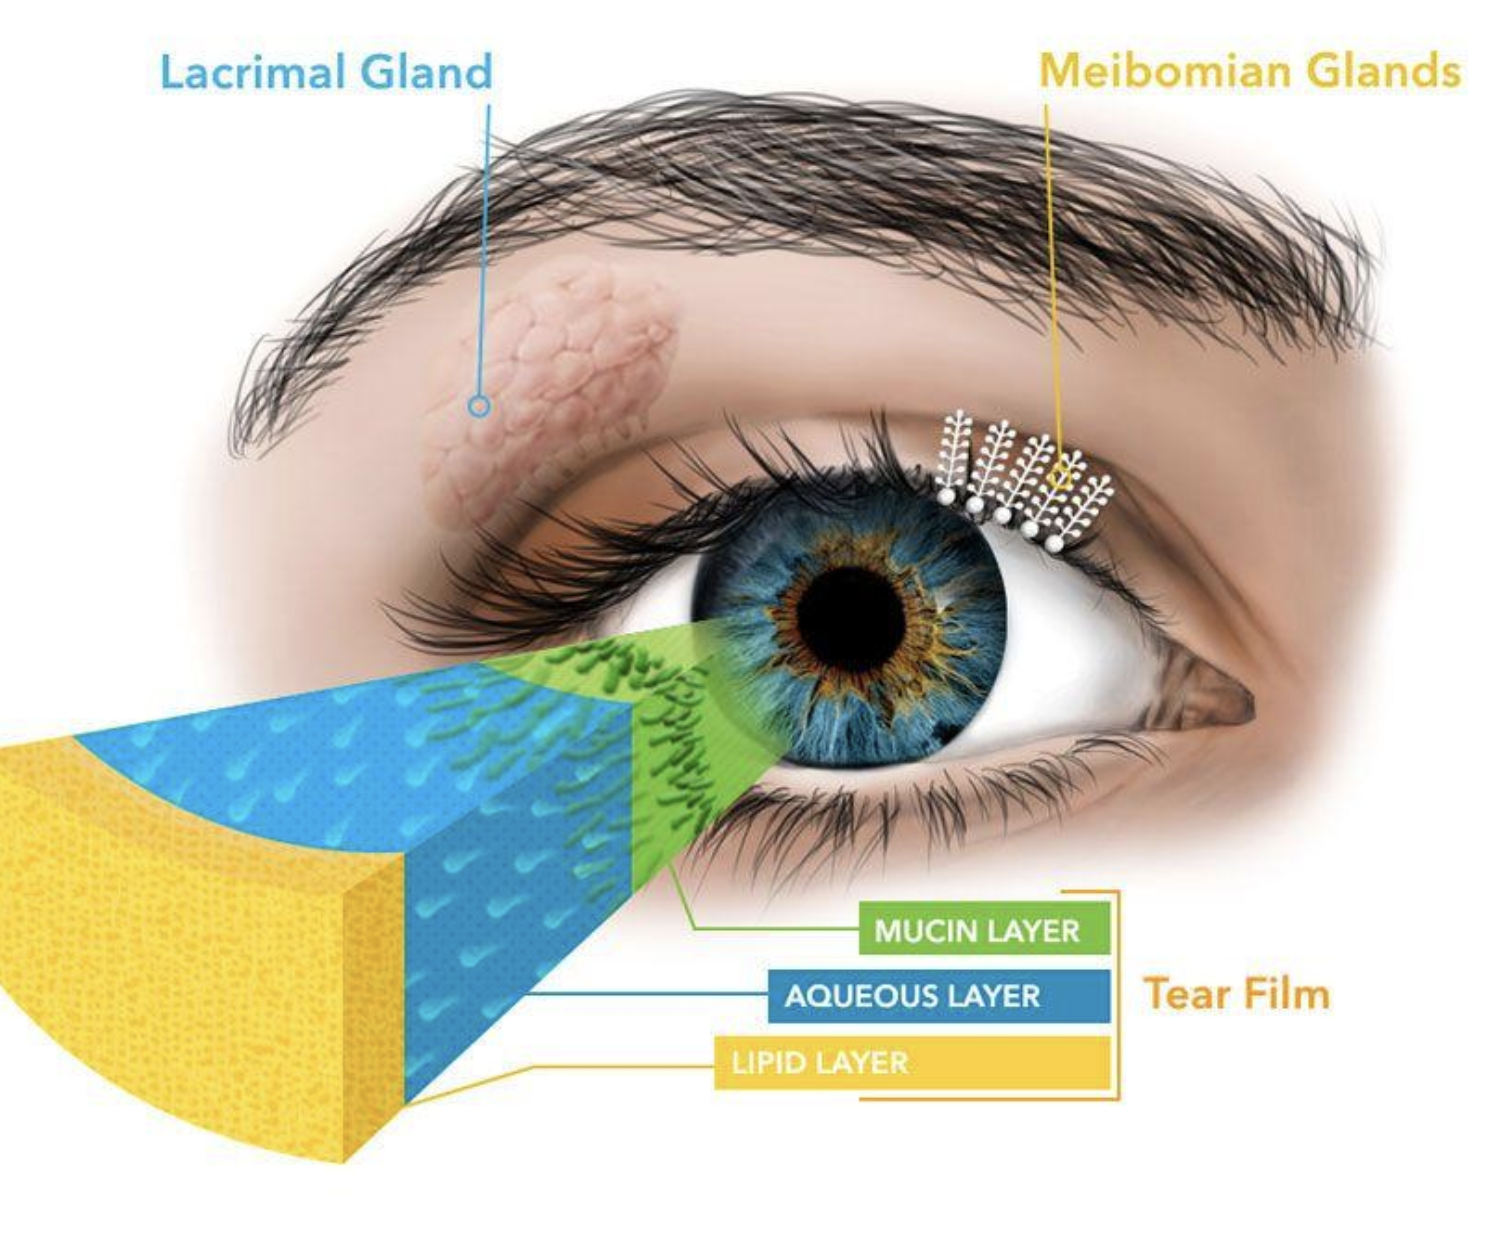

The human tear layer has three main layers. The mucin layer is closest to the eye. The aqueous or water layer is in the middle and the lipid or oil layer is the outermost.

Studies report that upwards of 80% of dry eyes are the result of a lipid layer deficiency. The oil for the lipid layer of the tears comes from the meibomian glands.

When these meibomian glands do not release the oil into the tears in an efficient manner we refer to that as a condition named meibomian gland dysfunction (MGD).